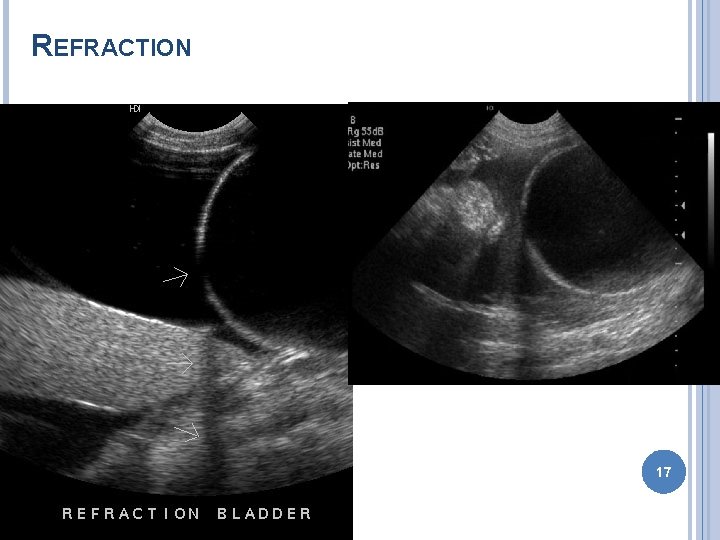

ARTIFACTS Improper machine settings – gain Reverberation � Mirror image – liver GB � Comet tail – gas bubble � Ring down – skin transducer surface Acoustic shadowing Acoustic enhancement Edge enhancement � Border of kidney 11

REFRACTION 17